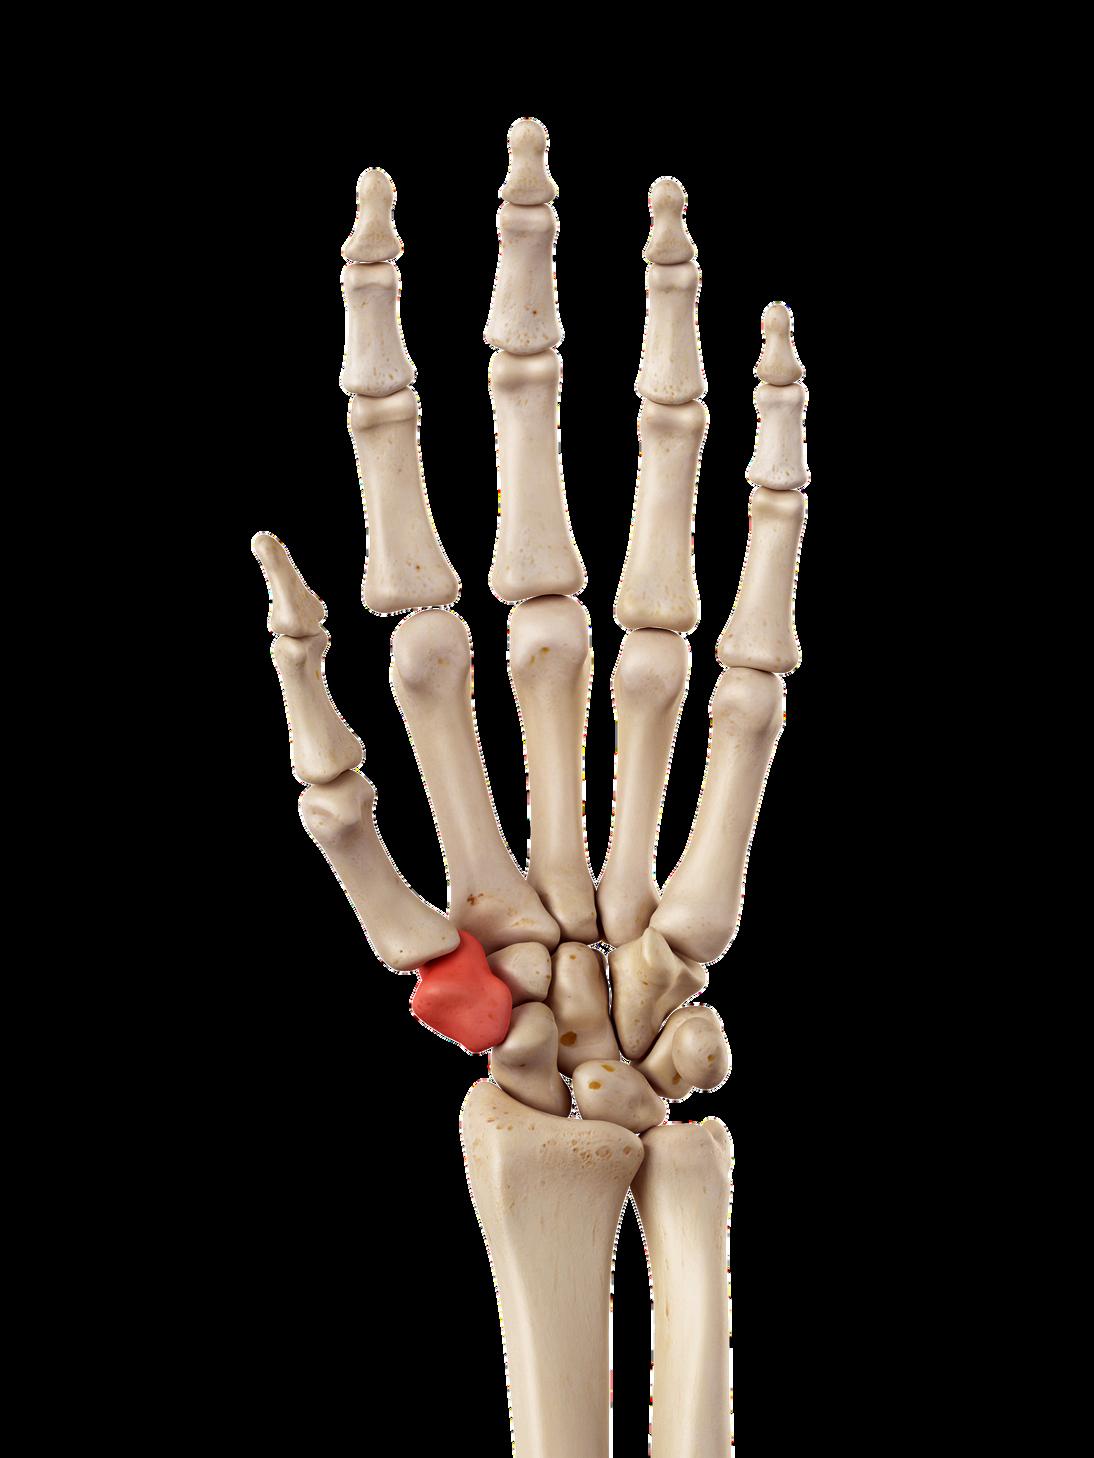

Providing structural support and stability for thumb movement, the trapezium is one of the eight small carpal bones of the wrist.

Degeneration or dysfunction of this bone most commonly due to arthritis can result in severe pain, reduced grip strength, and significantly impaired hand function

On February 16, 2026, CU Anschutz Orthopedics hand surgeons introduced a new surgical option for patients with advanced thumb carpometacarpal (CMC) arthritis performing the first joint preserving thumb prosthesis procedure in Colorado and the western United States

For decades, the standard surgical treatment for advanced thumb arthritis known as CMC arthroplasty or rhizarthrosis surgery has involved removing the trapezium bone at the base of the thumb and stabilizing the joint using a bundle of tendons. While effective at relieving pain, the procedure typically requires prolonged immobilization, with recovery measured in months, and may result in diminished pinch strength and altered thumb mechanics

The new approach replaces the diseased joint with a small, dual mobility ball and socket prosthesis rather than removing the trapezium Instead of reconstructing the joint space with tendon, surgeons implant the device directly into bone preserving anatomy and maintaining the thumb’s natural biomechanics

By embedding the implant into the trapezium and first metacarpal, surgeons aim to reduce surgical trauma, maintain joint stability, and accelerate functional recovery while helping patients retain a more normal sense of thumb strength and motion. Following surgery, the first Colorado patient a 58 year old woman with osteoarthritis was able to go home the same day with only a soft dressing, avoiding the cast or prolonged splinting typically required after traditional CMC arthroplasty Early recovery mirrored outcomes reported by European surgeons, reinforcing expectations for a faster, less restrictive rehabilitation process.